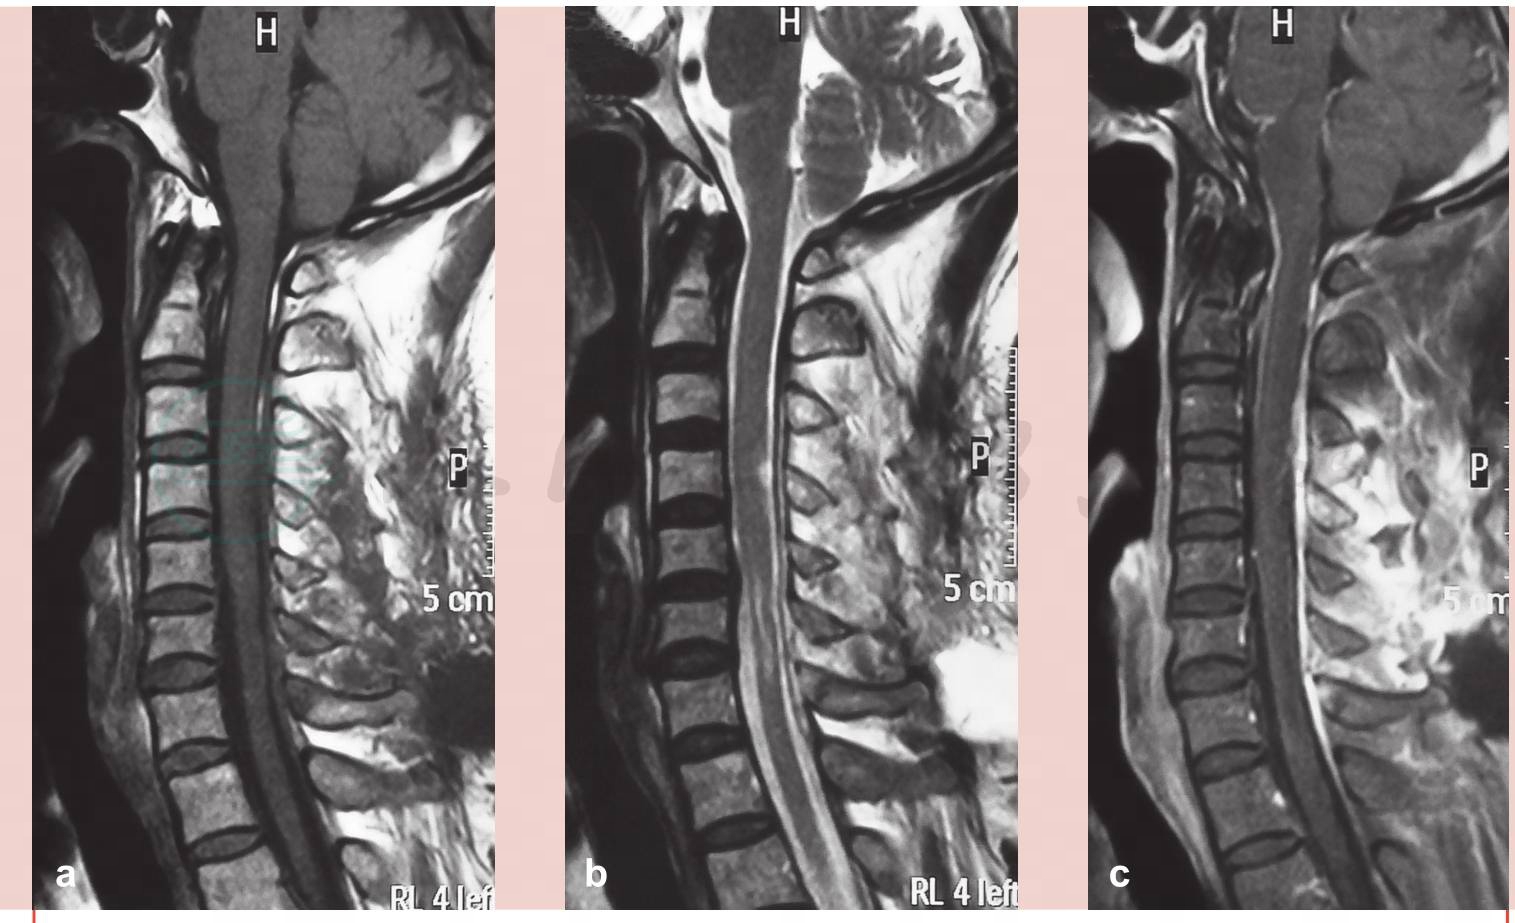

术前磁共振(MRI):C4-5脊髓左后、C6-7脊髓右后、T12-L1脊髓两侧、L5椎管内髓外硬膜下见多发团块状不均匀长T1长T2信号影,边界较清楚,相应水平脊髓受压,椎管有效前后径在正常范围(图1、图2)。

图1 术前颈部磁共振(MRI)

a. T1像;b. T2像;c.强化像